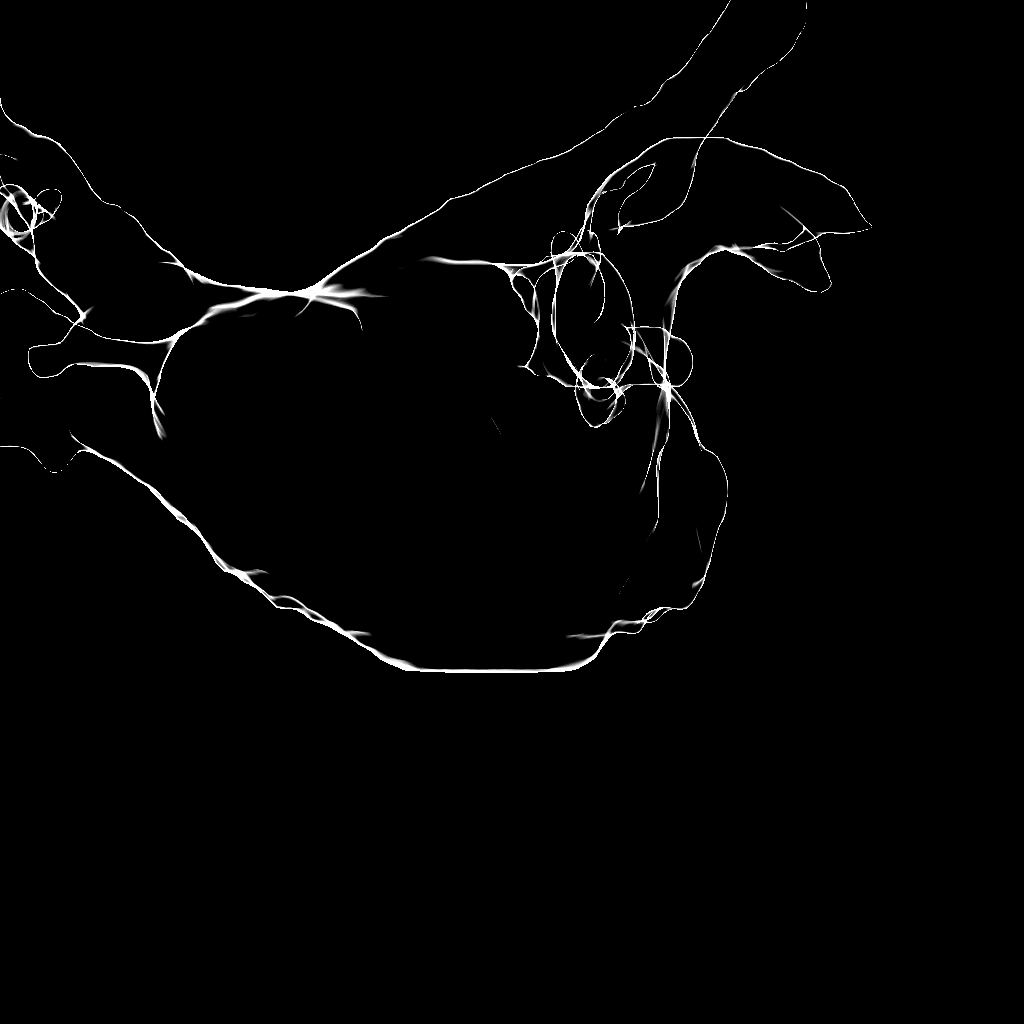

Refer to caption

Figure 2: Using the original image (a), a DSA image (b) is computed. After median filtering (c), the remaining motion artifacts from the catheter have vanished. Afterwards, all pixels are weighted by a sigmoid function (d) to get a homogeneous value distribution inside the contrasted area. Edges are extracted using derivatives of Gaussian with a large kernel size (e). Finally, the similarity to the rendered edges (f) is evaluated.